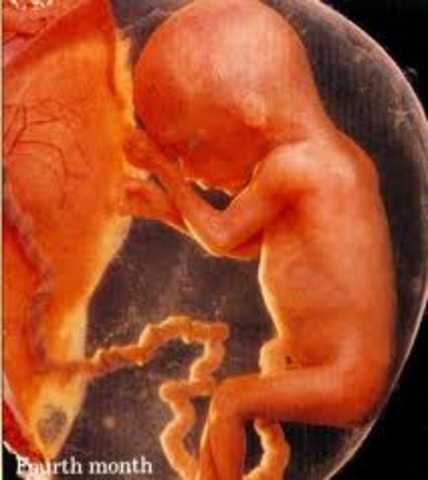

• Month four - baby

Month four - baby

About 3 inch, It can suck its thumb, swallow hiccup and move around. Its facial features become clearer.